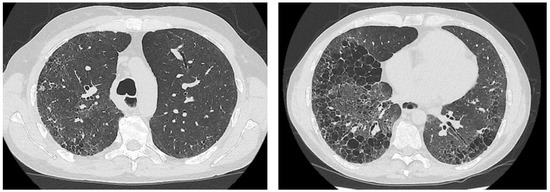

2. Case Presentation